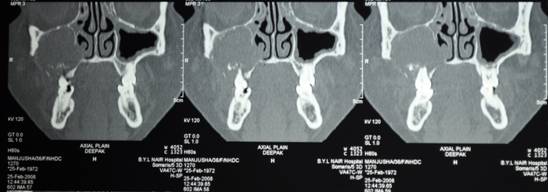

C T SCAN CORONAL SECTION SHOWS THE EXTENT OF DISEASE

C T SCAN CORONAL AND AXIAL SECTION SHOWS EXTENT OF DEFECT AFTER RESECTION